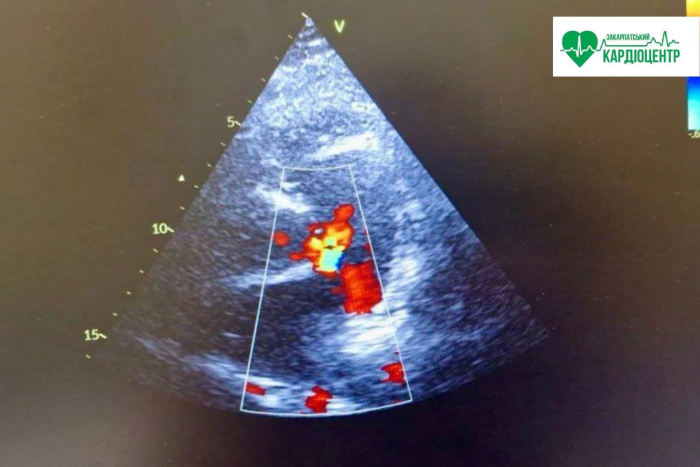

– Основним методом діагностики є УЗД серця (ехокардіографія). Додатково можуть застосовувати ЕКГ, МРТ, КТ та інші методи обстеження.